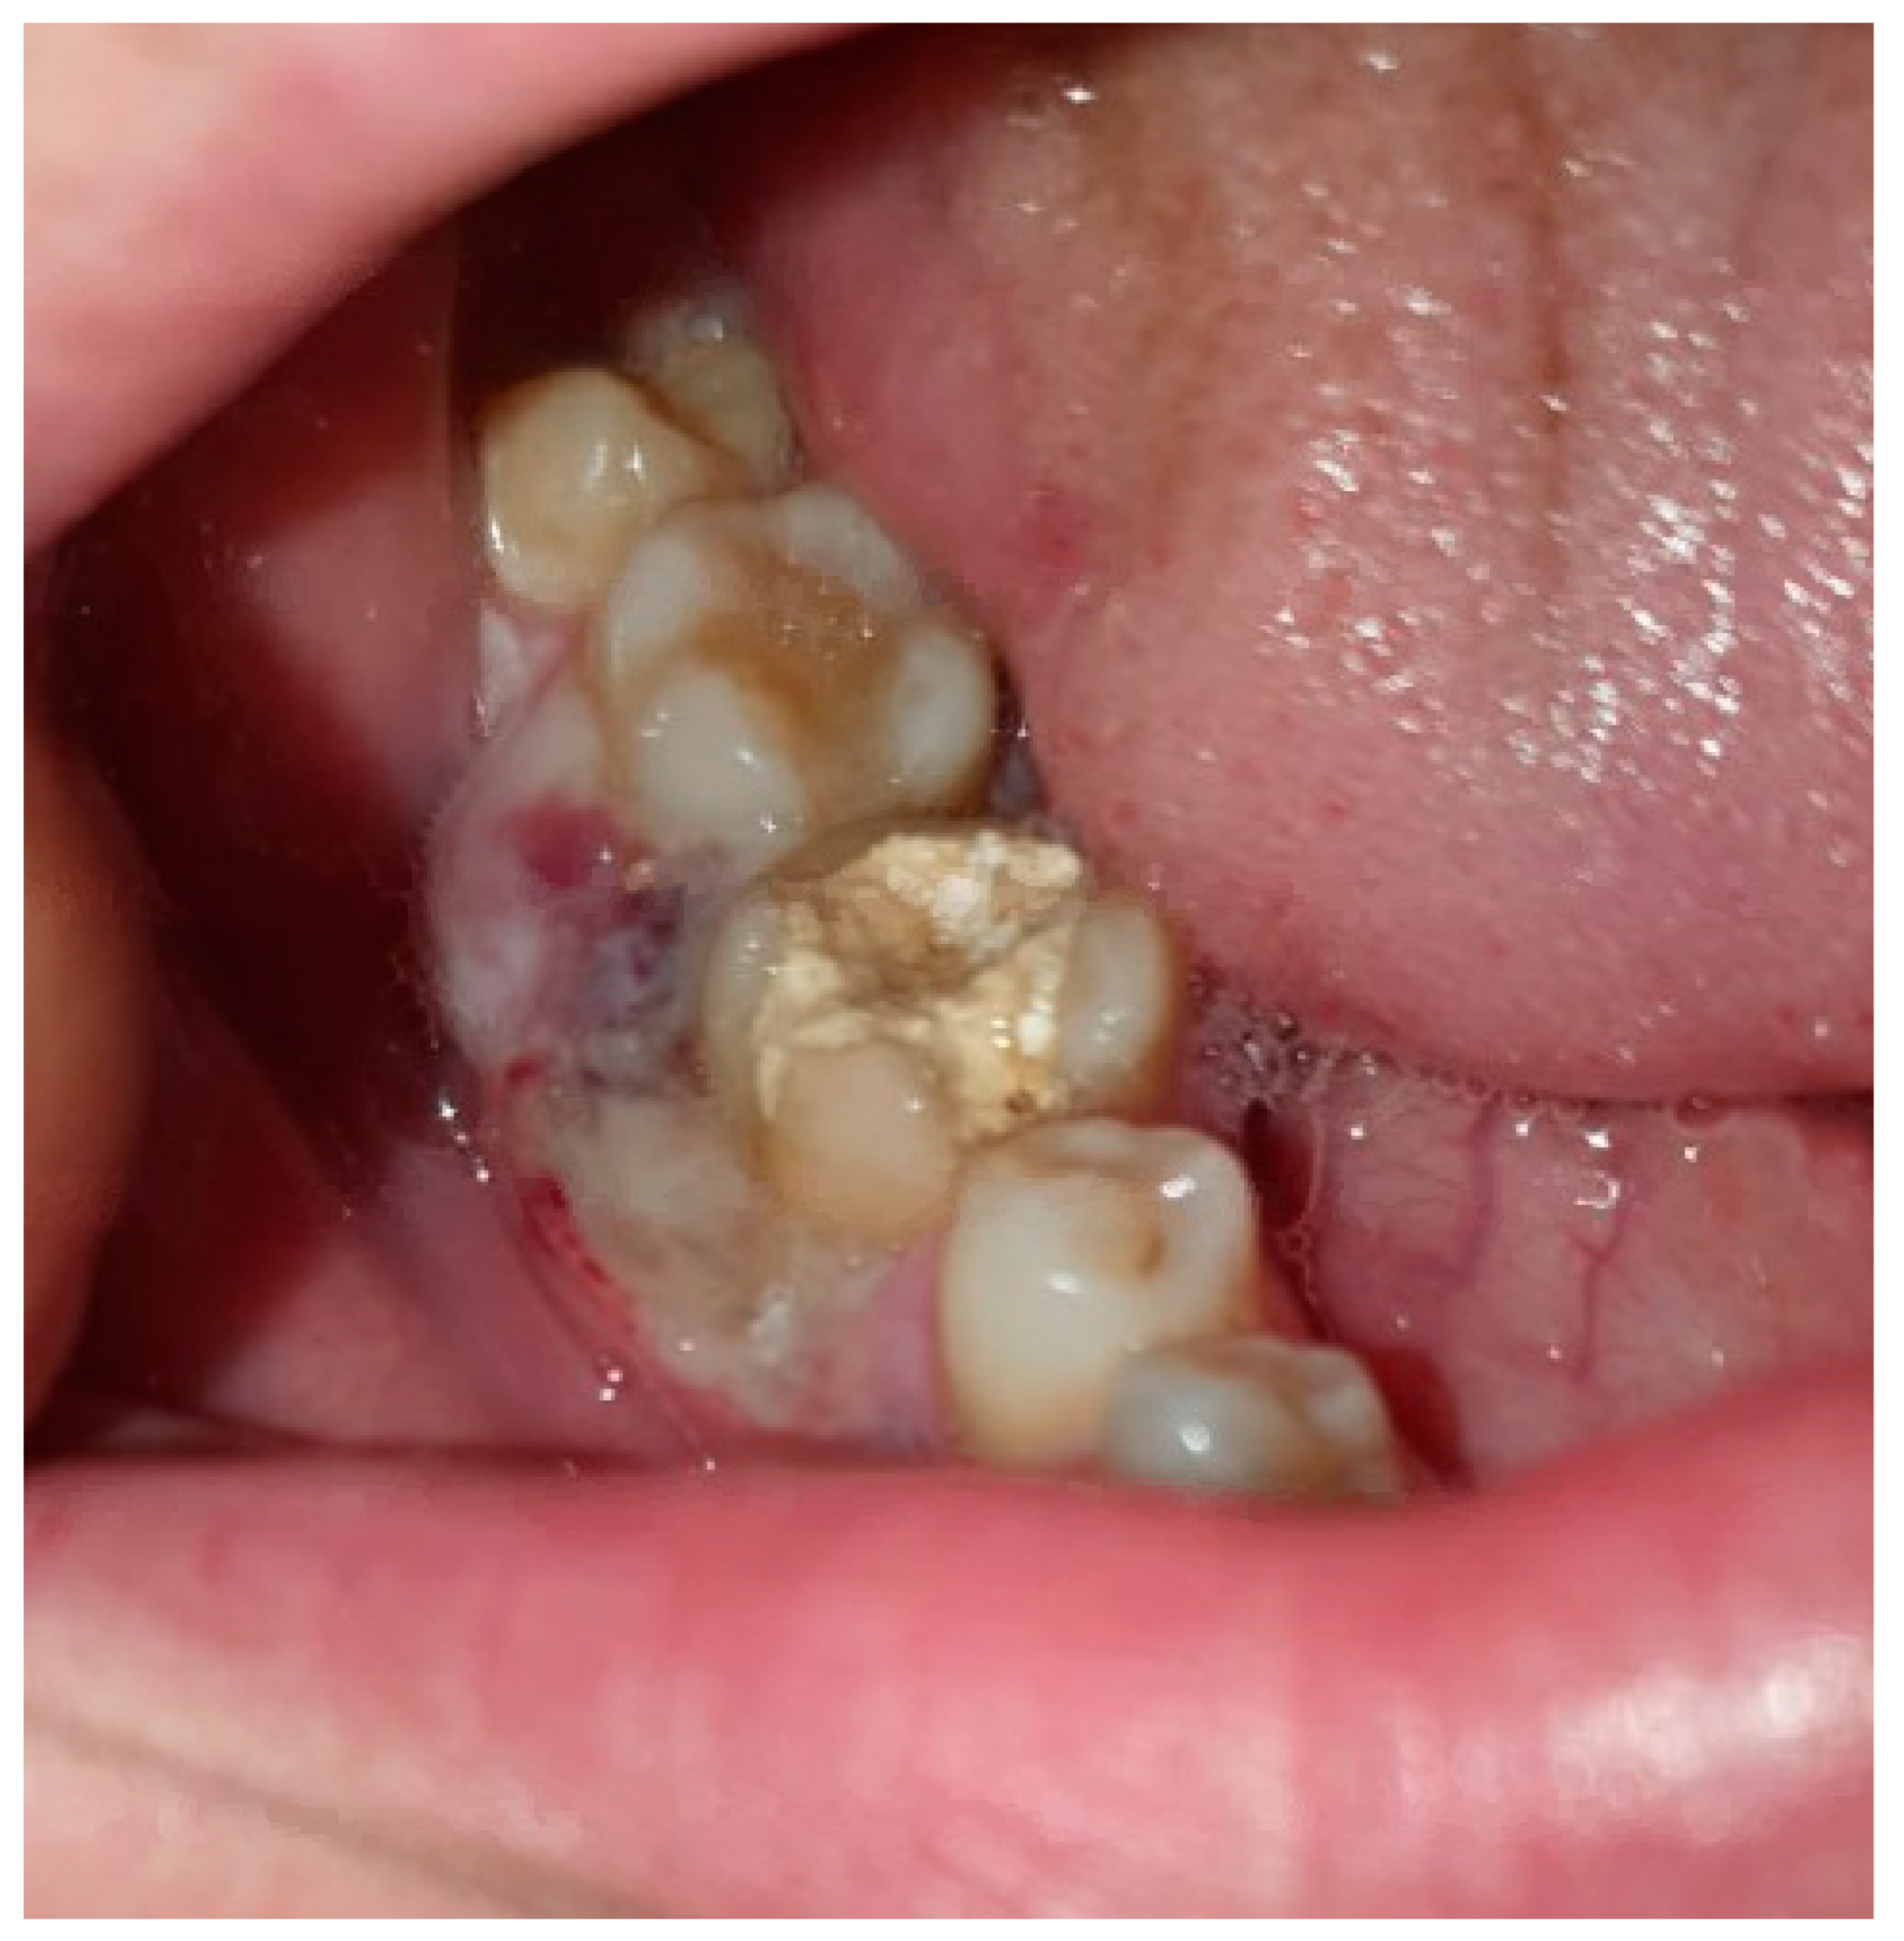

2. Case Presentation

2.1. Clinical Examination

2.5. Follow-Up and Outcomes